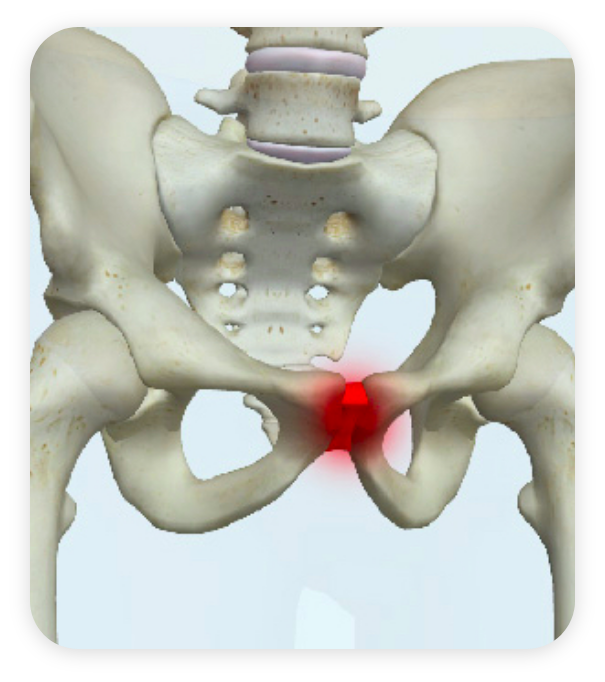

A pubalgia é uma condição caracterizada por dor crônica na região da virilha, parte inferior do abdômen, bacia, coxas e áreas genitais. Popularmente chamada de pubeíte ou pubalgia de atleta, não se trata de uma hérnia, apesar do termo “hérnia do esporte” ser usado equivocadamente. Essa dor surge devido à inflamação ou lesão nos tendões e músculos que ligam a musculatura abdominal e os adutores da coxa à pelve, causando desconforto constante. A pubalgia é comum em atletas que realizam movimentos repetitivos de torção, salto ou chute, mas pode acometer qualquer pessoa após esforço físico excessivo ou desequilíbrio muscular na região pélvica.

O diagnóstico da pubalgia inicia-se com a avaliação clínica detalhada, baseada nos sintomas relatados e exame físico, no qual o médico avalia a dor ao pressionar a sínfise púbica (articulação anterior da bacia) e ao realizar movimentos que contraem o reto abdominal e os adutores da coxa contra resistência. Devido à semelhança dos sintomas com outras doenças, podem ser solicitados exames de imagem como raio X, para identificar alterações ósseas, e ressonância magnética, que permite avaliar inflamações nos tendões e músculos, além de diferenciar pubalgia de outras condições, como hérnias inguinais. O tratamento é indicado principalmente para pacientes com dor persistente, limitação funcional e histórico de atividades físicas intensas ou movimentos repetitivos que agravem a região pélvica.